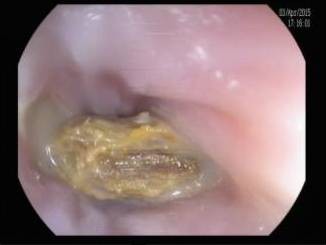

过去的两周内,西安交大二院内镜室接诊了14例上消化道异物患者,他们中年龄最大者80余岁,最小者才10岁,造成他们痛苦的罪魁祸首竟然都是枣核。生活中我们经常碰见鱼刺、肉骨头、假牙等卡在食管或是小儿误吞异物(硬币、发卡等)事件,医学上称为上消化道异物。在内镜检查和治疗开展以前,传统的处理方法是紧急外科剖腹或开胸手术取出异物或口服某些食物促使异物自然排出,但以上方法危险性大、并发症多、患者痛苦。随着内镜技术的进展和设备的普及,内镜下消化道异物取出术已经成为一门成熟的治疗技术,

交大二院消化内镜室已成功地为众多的上消化道异物的患者解除了痛苦.虽然经常加班加点,但看着患者担惊害怕地走进胃镜室,高高兴兴地走出胃镜室,再晚再累他们也觉得欣慰.